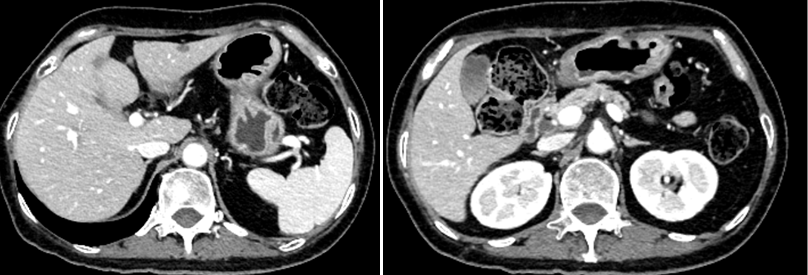

2024年3月23日复查CT提示胃窦壁稍增厚,较厚处约1.2cm。肝左叶见数个结节影,大者位于肝左内叶,大小约1.6*1.3cm(图3)。

疗效评价:PR。

图3. 腹部CT检查(2024年3月23日)

2024年6月9日复查CT提示胃窦壁稍增厚,较厚处约0.8cm;肝左叶见数个结节影,大者位于肝左外叶下段,大小约1.0*0.6cm(图4)。